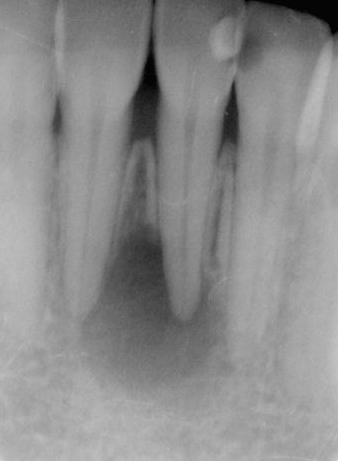

図1b 根管治療後1年経過しても病変の縮小がなく、 歯根端切除と嚢胞摘出を行った